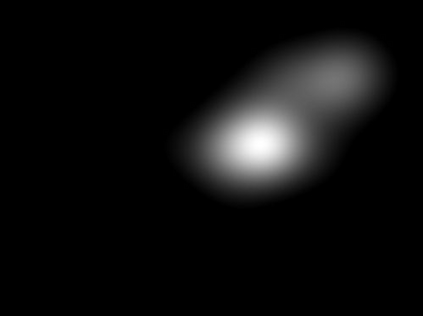

The way humans attend to, process and classify a given image has the potential to vastly benefit the performance of deep learning models. Exploiting where humans are focusing can rectify models when they are deviating from essential features for correct decisions. To validate that human attention contains valuable information for decision-making processes such as fine-grained classification, we compare human attention and model explanations in discovering important features. Towards this goal, we collect human gaze data for the fine-grained classification dataset CUB and build a dataset named CUB-GHA (Gaze-based Human Attention). Furthermore, we propose the Gaze Augmentation Training (GAT) and Knowledge Fusion Network (KFN) to integrate human gaze knowledge into classification models. We implement our proposals in CUB-GHA and the recently released medical dataset CXR-Eye of chest X-ray images, which includes gaze data collected from a radiologist. Our result reveals that integrating human attention knowledge benefits classification effectively, e.g. improving the baseline by 4.38% on CXR. Hence, our work provides not only valuable insights into understanding human attention in fine-grained classification, but also contributes to future research in integrating human gaze with computer vision tasks. CUB-GHA and code are available at https://github.com/yaorong0921/CUB-GHA.